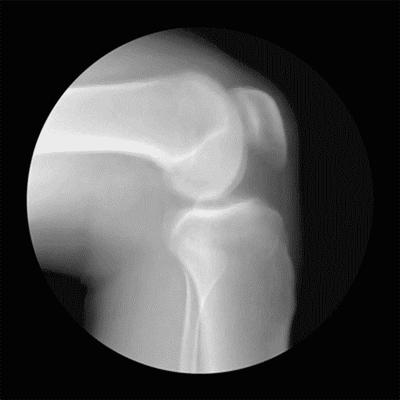

关节炎早期为关节软骨、半月板的磨损

关节软骨、半月板为骨与骨之间的垫子

半月板的中心部位、关节软骨无血管

它就像一块海绵

其营养代谢靠挤压、回弹

排出代谢废物、回吸营养